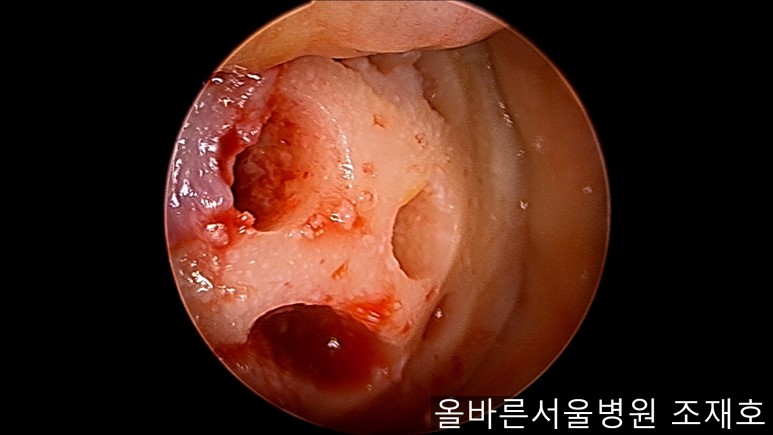

通过关节镜图像可看到:由于内侧股骨髁软骨损伤骨头已经显露出来。

胫骨上端的软骨损伤严重,也露出了骨头。

正是缺失软骨的部位碰到一起,引发剧烈疼痛,腿部逐渐变形。